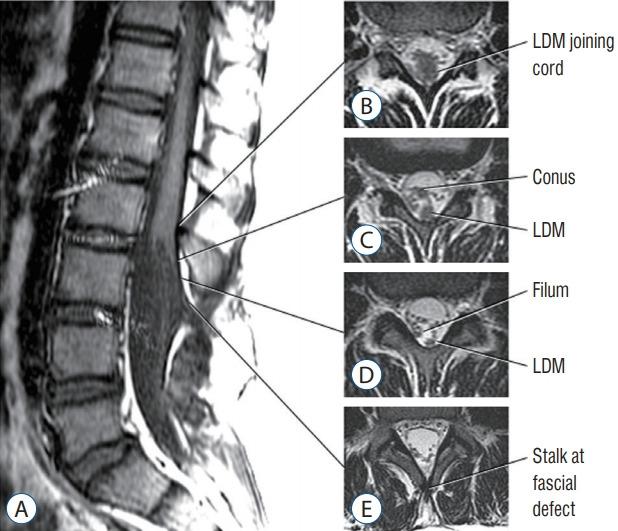

Spinal dysraphic lesions due to focal nondisjunction in primary neurulation are commonly encountered in paediatric neurosurgery, but the "fog-of-war" on these conditions was only gradually dispersed in the past 10 years by the works of the groups led by the senior author and Prof. Kyu-Chang Wang. It is now clear that limited dorsal myeloschisis and congenital spinal dermal sinus tract are conditions at the two ends of a spectrum; and mixed lesions of them with various configurations exist. This review article summarizes the current understanding of these conditions' embryogenetic mechanisms, pathological anatomy and clinical manifestations, and their management strategy and surgical techniques.

由于原发性神经管形成过程中的局灶性不分离导致的脊柱裂病变在小儿神经外科中很常见,但在过去10年中,由资深作者和王宇辰教授领导的团队的工作才逐渐驱散了这些病症上的“战争迷雾”。现在已经明确,有限性背侧脊髓裂和先天性脊柱皮样窦道是同一谱系两端的病症;并且存在各种形态的它们的混合病变。这篇综述文章总结了目前对这些病症的胚胎发生机制、病理解剖和临床表现,以及它们的治疗策略和手术技术的认识。